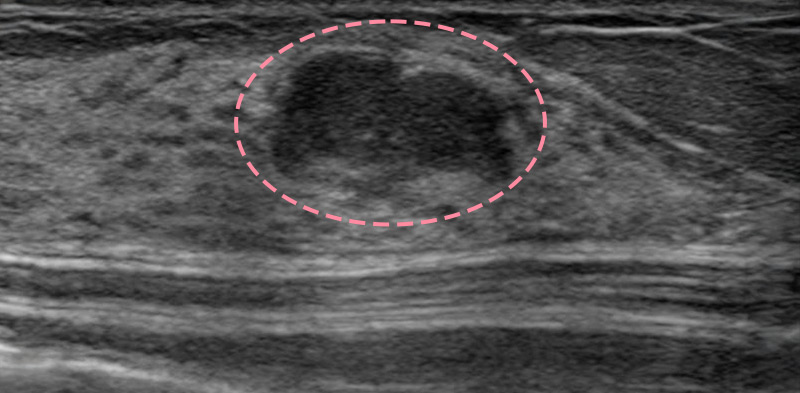

매우 빠르게 자라는 유방 종양 수술을 위해 외국에서 내원한 17세 환자의 사례입니다.

3cm 이상의 유방 종양은 외과적 수술로 제거하는 것이 원칙이고, 대부분의 경우 대학병원으로 연계됩니다.

그러나 한송이 원장은 대학병원에서의 고난도 시술 경력을 다수 보유하고 있어 크기가 큰 종양도 맘모톰 시술로 가능하였습니다.

3번에 걸쳐 맘모톰시술을 시행한 결과 성공적으로 제거를 마칠 수 있었습니다. 외과적 절제로 생길 수 있었을 흉터를 원치 않으셨던 환자와 보호자분 모두 시술 결과에 만족하셨습니다. 매년 추적 검사를 시행하고 있으며, 깨끗이 제거된 상태를 잘 유지하는 중입니다.